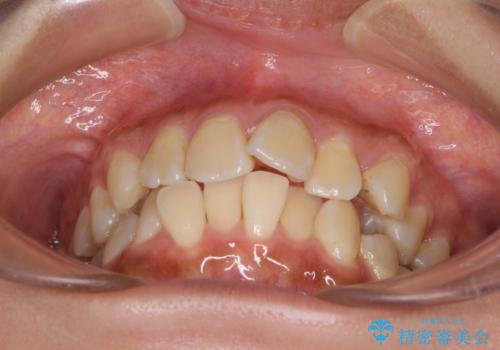

デコボコで磨きにくい前歯をスッキリと インビザライン矯正

- 虫歯が多く、磨きにくい歯並びを改善したいとのことで来院された患者様です。

歯列は叢生が認められる程度でしたが、やや前突感があったので、少しでも口が閉じやすくなるように仕上げる方針としました。

歯磨きしやすくなるとともに、飛び出していた前歯も引っ込めて整えることができました。